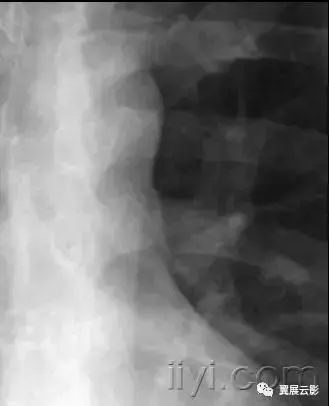

五十五、纵隔气肿

病理:纵隔气肿是指气体存在于食管和气管支气管树之外的纵隔组织内,可以是肺泡的自发破裂导致气体沿着气管血管间质进入纵隔所致。纵隔气肿与哮喘、重度咳嗽,或者机械通气有着明显联系。

平片和CT:纵隔气肿在胸片上显示为带状的透亮影,大多数垂直走向,见图。部分低信号条带影可以勾勒出血管和支气管的边界(参加心包气肿)